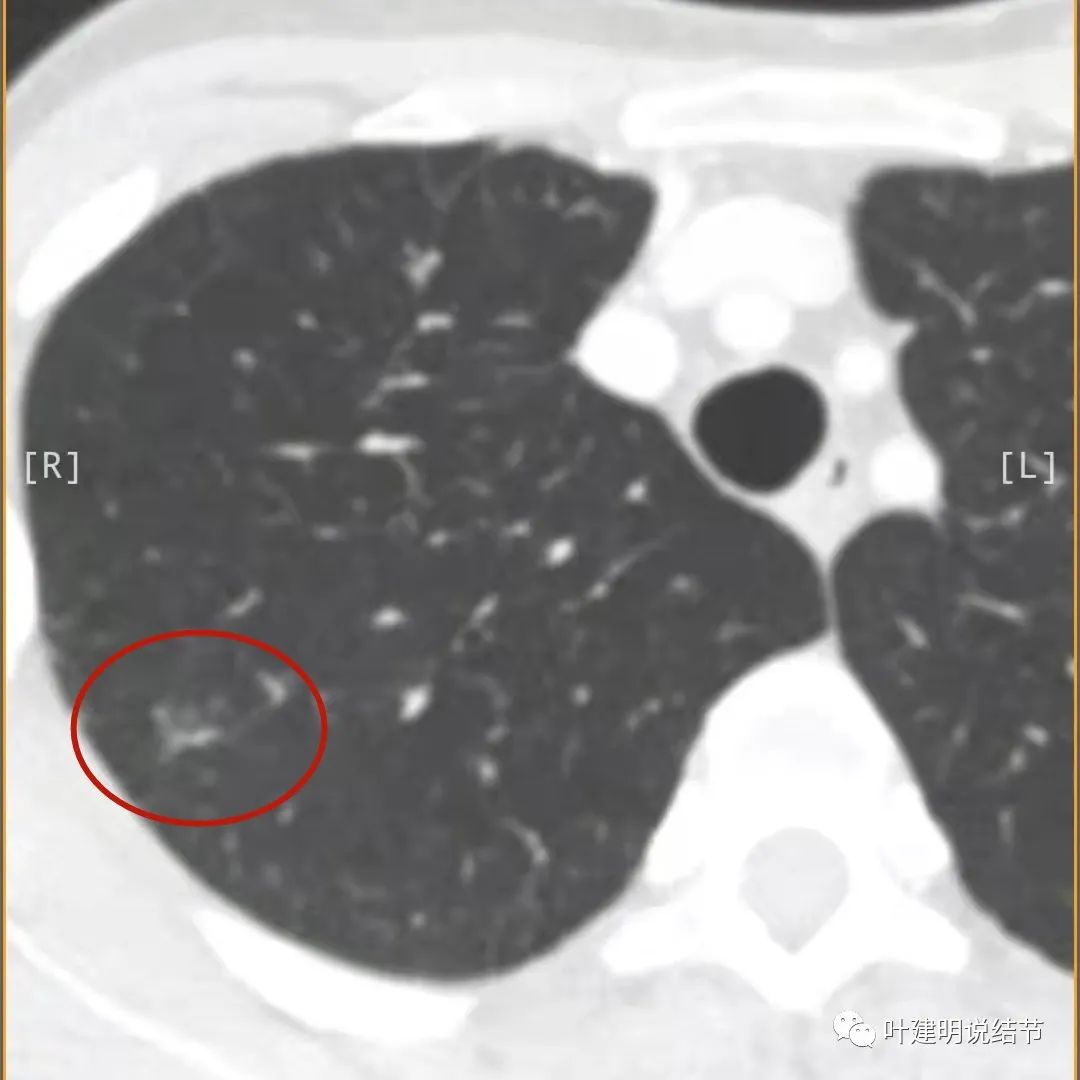

病灶出现,模糊的磨玻璃影

部分密度过高,且呈条状

邻近胸膜有增厚(蓝色箭头),主病灶边界较清(红色箭头),实性部分密度过高(粉色箭头),旁边有磨玻璃影,散且模糊(砖色箭头)